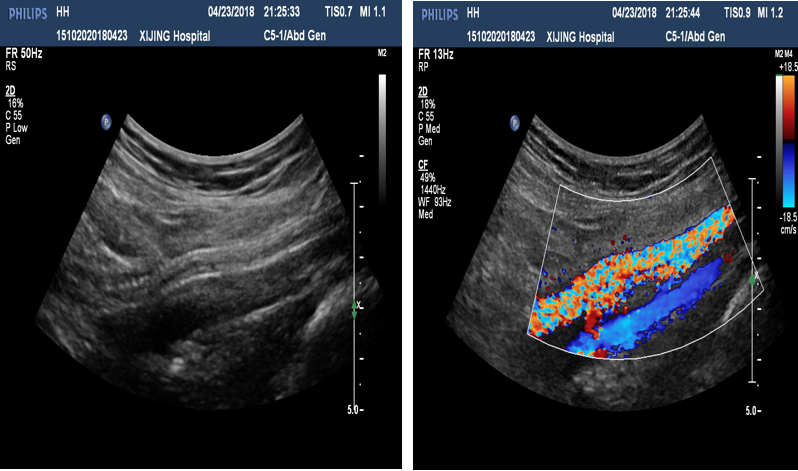

图:a) 穿刺后导丝置入;

图:b) 吸栓装置定位;

图:c) 球囊扩张股浅动脉时球囊远心端显像;

图:d)球囊扩张股浅动脉开口处显像,同时附带血流显像;

图:e)术前评估时腘动脉未见血流图像;

图:f)经吸栓、球囊扩张等治疗措施后腘动脉血流图像